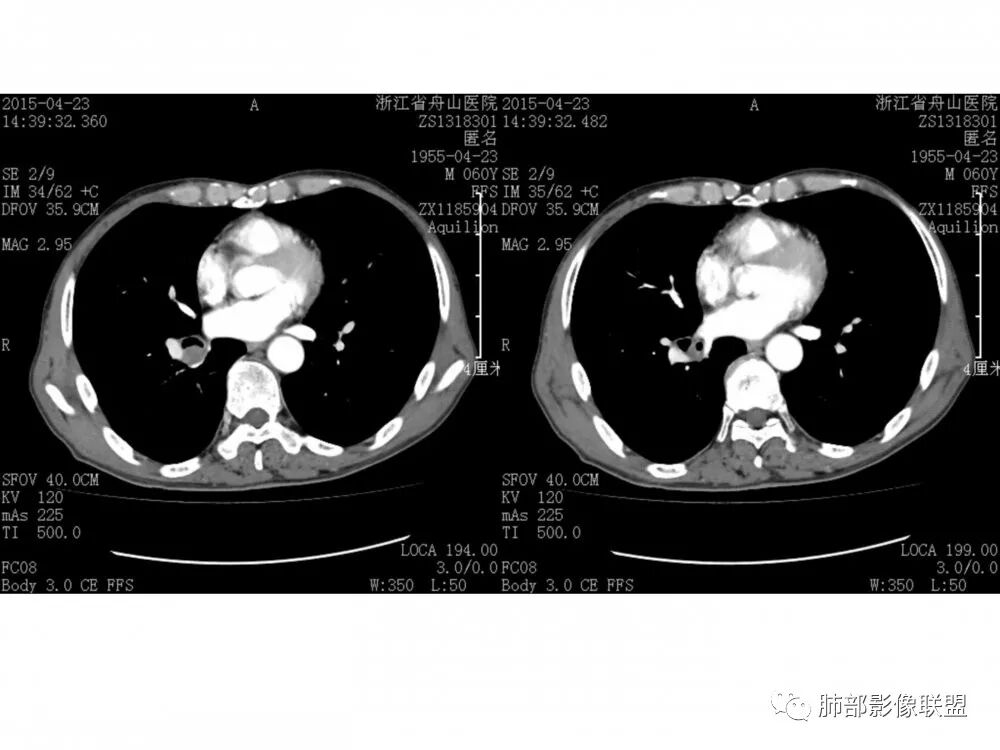

右肺下叶支气管开口新生物,轴位管腔及纵向基底干大部分受累狭窄,支气管管壁破坏明显,强化较低不均匀,肺门、7组、4R淋巴结肿大,考虑恶性支气管腔内肿瘤,鳞癌可能性大,需要与类癌、涎腺类肿瘤鉴别

老年男性,60岁,右下肺门肿块,右下支气管粘膜下生长,并堵塞,无明显阻塞性肺炎和肺不张,早期多发淋巴结转移,似不均匀强化。综合看恶性程度高,考虑大细胞癌,一个不支持点,大细胞癌外周多见。

男,60岁,右肺下叶支气管开口新生物,轴位管腔及纵向基底干大部分受累狭窄,支气管管壁破坏并突破形成腔外肿块,强化较低不均匀,右肺门、7组、4R淋巴结肿大,考虑恶性没问题,鳞癌可能性大,类癌、粘液表皮样癌,乳头状瘤待排。

右肺下叶支气管不规则软组织肿块,病灶沿支气管生长,有一定的张力,部分包绕支气管壁,增强病灶内可见中度强化,内部有延迟强化的特点,周围淋巴结增大,诊断恶性病变无疑,远端无明显支气管阻塞,主要考虑粘液表皮癌,腺样囊腺癌,鳞癌之间鉴别,病灶有类似神经源性病变生长方式,腺样囊腺癌,其次考虑鳞癌或粘液表皮癌。

流心明智

老年男性,右肺下叶支气管开口新生物,基底干及中间支气管受累狭窄,支气管管壁破坏明显,强化低,不均匀,肺门、7组、4R淋巴结肿大,考虑恶性支气管腔内肿瘤,小、鳞可能大,需与类癌、粘表等鉴别。

右肺下叶支气管开口新生物,轴位管腔及纵向基底干大部分受累狭窄,支气管管壁破坏并突破形成腔外肿块,血管累及变细,肉眼观轻度强化,右肺门、纵膈淋巴结肿大,恶性没问题,阻塞性炎症不明显,类癌强化明显不支持,老年男性,首先考虑小细胞癌,鉴别不典型鳞癌和腺癌。

病理结果:鳞癌